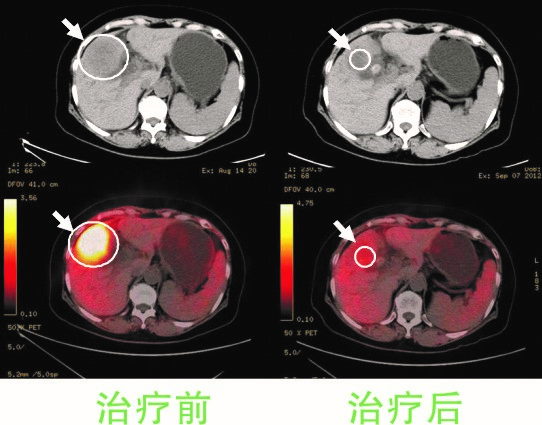

女性,58岁,胆囊癌,伴随腹腔淋巴结多处转移。左两图为A45肿瘤治疗前的CT、PET-CT图像,右两图为治疗后图像,治疗后18F-FDG代谢迅速恢复到正常水平,原发病灶和转移病灶快速缩小。